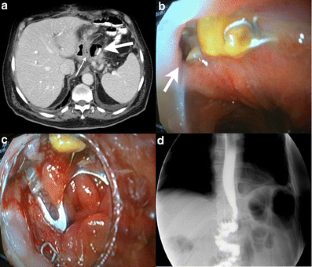

Fig. 2